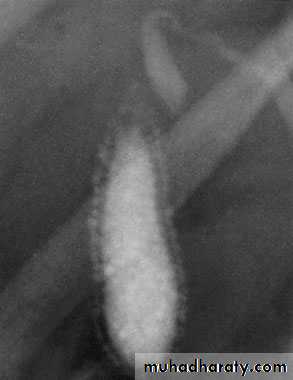

Peroperative cholangiographyDuring open or laparoscopic cholecystectomy, a catheter can beplaced in the cystic duct and contrast injected directly into thebiliary tree. The technique defines the anatomy and is mainlyused to exclude the presence of stones within the bile ducts .